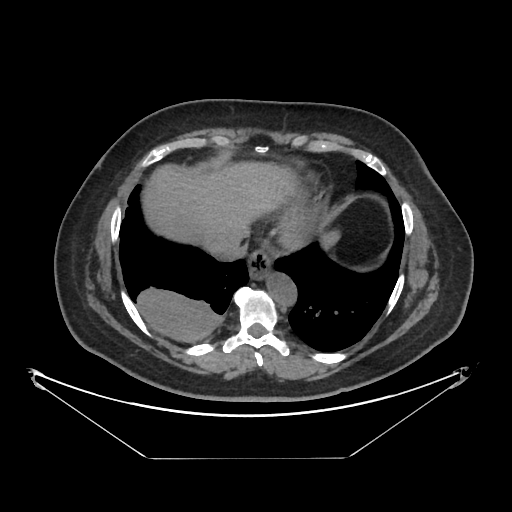

Image Grid

4Γ—3 grid: Rows show different image types (Original NATIVE, Reconstructed NATIVE, Original VENOUS, Generated VENOUS), Columns show windowing techniques (No Window, Lung Window, Mediastinum Window)

Generated VENOUS CT scan (A→B translation)

Full window (WL 1023.5, WW 4095 β†’ Low βˆ’1024, High +3071)